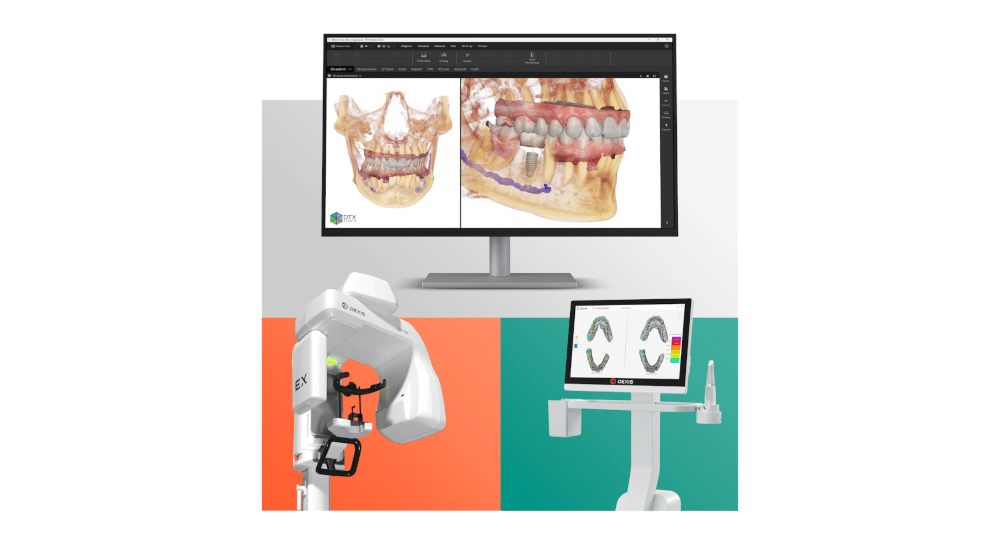

*Nouvelle approche de la chirurgie guidée : l’expertise par un logiciel de navigation 3D d’une planification sur modèle. Le projet planifié en amont sera transféré à l’image par un guide radiologique et analysé par le logiciel. Les rectifications d’axes décidées sur l’image seront facilement transposées en chirurgie par une modification du guide radiologique sur modèle. Ce guide permet un geste opératoire cadré et précis sans le stress inhérent aux actes effectués à main levée. Son coût est de 5 à 10 fois moindre que la majorité des autres systèmes.